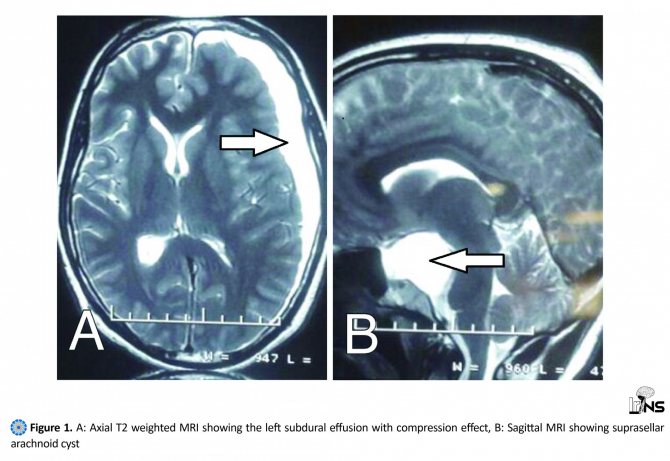

Как выглядят арахноидальная и ретроцеребеллярная кисты.